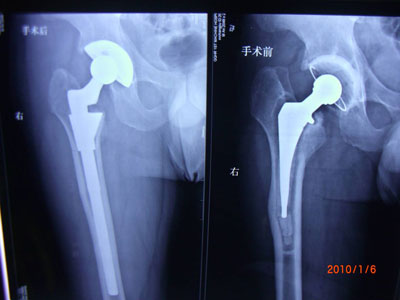

手术虽可切除骨刺,但仅限于骨赘过大或因关节常被“卡死”,经保守治疗无效者,或出现关节严重疼痛、畸形、关节不稳定、屈曲挛缩和严重肌萎缩者。这时可选择手术切除骨刺或关节鼠摘除术、关节成形术、关节融合术或人工关节置换术。但手术本身也是一种创伤,有些患者会因此造成无菌性炎症,而刺激骨质增生,甚至增生得更快。